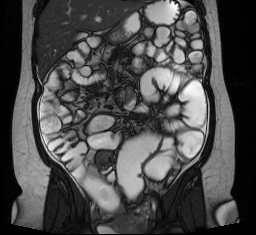

Enterografía por RMN

La enterografía por RMN es un tipo especial de resonancia magnética por imágenes (RMN) en la que se usa un agente de contraste para producir imágenes del intestino delgado.

Los médicos usan la enterografía por RMN para identificar y localizar:

• la presencia de y las complicaciones consecuencia de la enfermedad de Crohn y otras enfermedades inflamatorias del intestino

• inflamación

• causas de sangrado y anormalidades vasculares

• tumores

• abscesos y fístulas

• obstrucciones intestinales